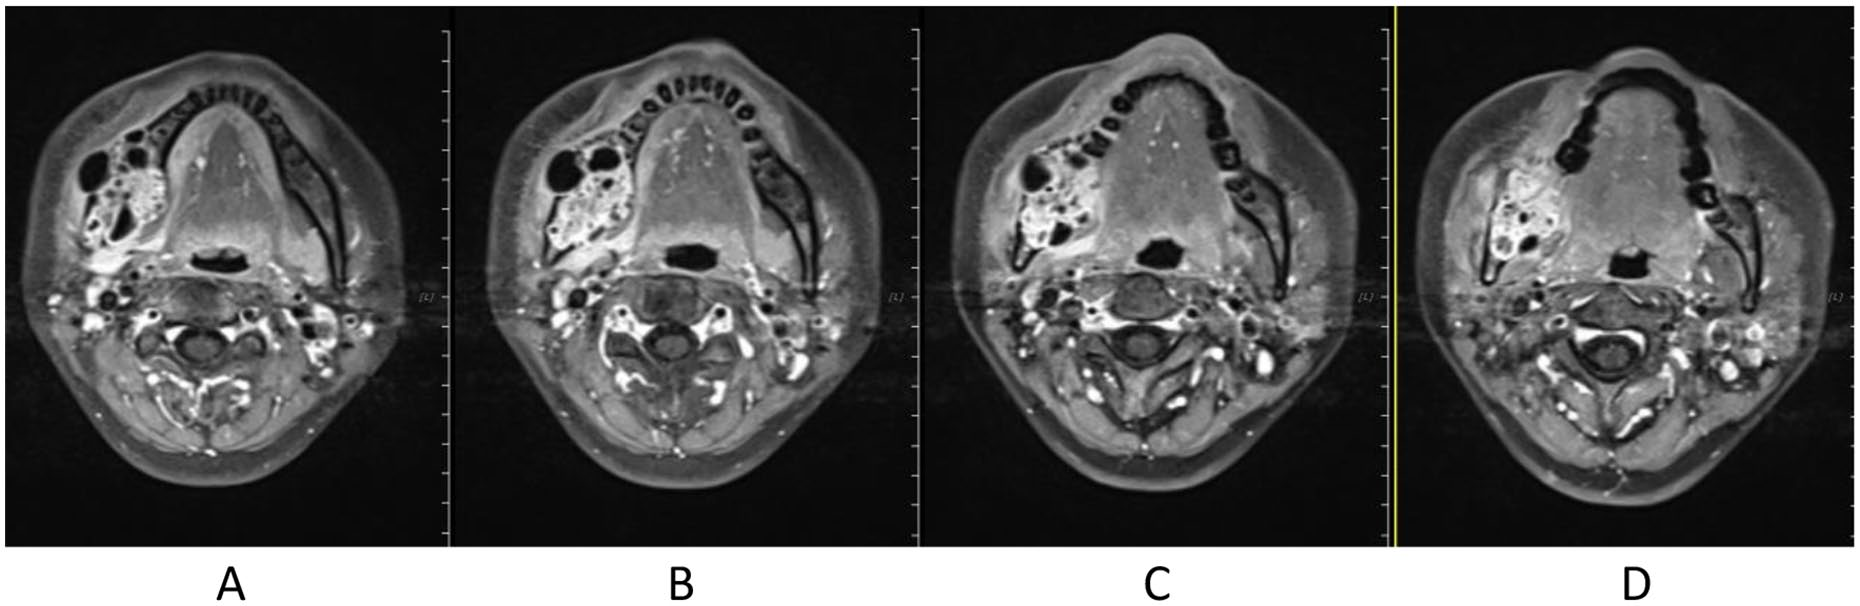

Treatment was tolerated well. During and after CIRT, there was only grade 2 skin (Figure 2) and oral mucosa acute adverse event, and no grade ⩾3 RTOG acute effect. During and after CIRT, her pain in the right mandible is continued but never aggravated, but painkiller is not needed; 6-month post completion of radiotherapy, she was in a very good clinical state, and the pain in the right mandible resolved completely. One to three months after CIRT, there were no significant changes of tumor size on MRI (Figures 3–6), just intensity of contract enhancement gradually diminished on contract-enhanced T1-weighted MRI; from 6months on, the size of the tumor decreased gradually (Figure 7); up to 16months after CIRT, it regressed to 3.6cm×3.2cm×1.7cm; and on 19months after CIRT, it regressed to 3.6cm×3.2cm×1.7cm, and the efficacy evaluation is PR (partial response) (Figures 8–10).

Figure 3. Before CIRT (2020-04) different slices of Contrast-enhanced MR T1: A. Contrast-enhanced MR T1, B. Contrast-enhanced MRI, TWI1, C. Contrast-enhanced MR T1, D. Contrast-enhanced MR T1

Figure 4. After CIRT.